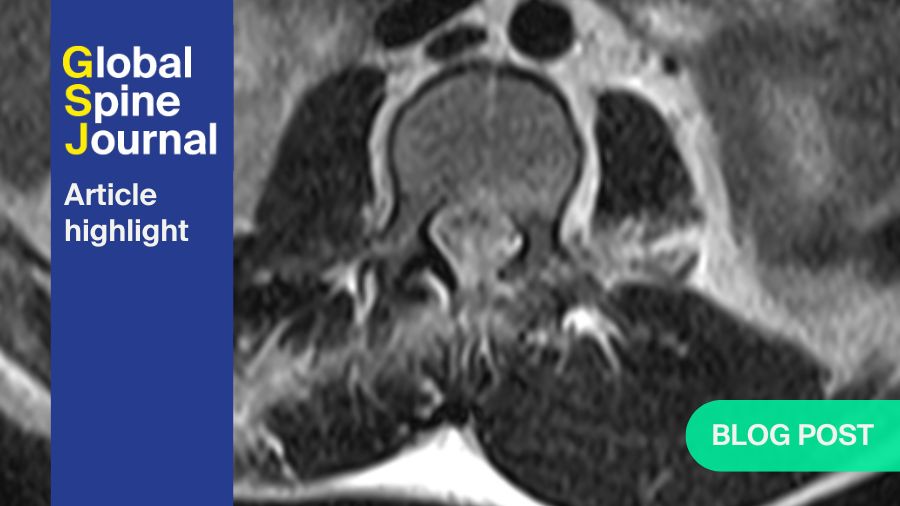

Modic changes: updated insights into back pain, MRI diagnosis, surgical outcomes, and emerging treatments

BY DR PETER M. UDBY